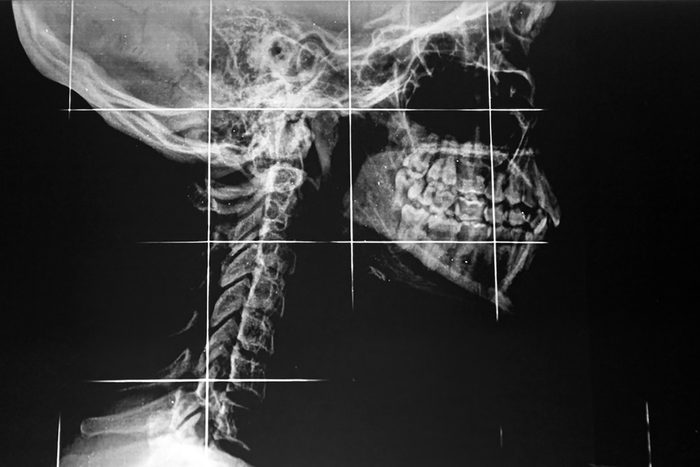

TMD

Temporomandibular joint disorder, abbreviated as TMD (also known as TMJ), affects the joints that connect the jawbone to the skull. It is one of the common jaw pain causes that is characterized by pain and restricted movement. Its symptoms can significantly affect the quality of life. Typical symptoms include pain and tenderness in the jaw joint area, the neck, the shoulders, the face, and the ear, as well as clicking sounds. Traditional treatments for TMD include muscle relaxants, a mouth guard, and dental procedures to correct bite problems and balance biting surfaces, according to the ADA. Patients can also try home remedies, including over-the-counter medications, heat or cold packs, and relaxation therapy to manage the pain. Here are more home remedies for every ailment.